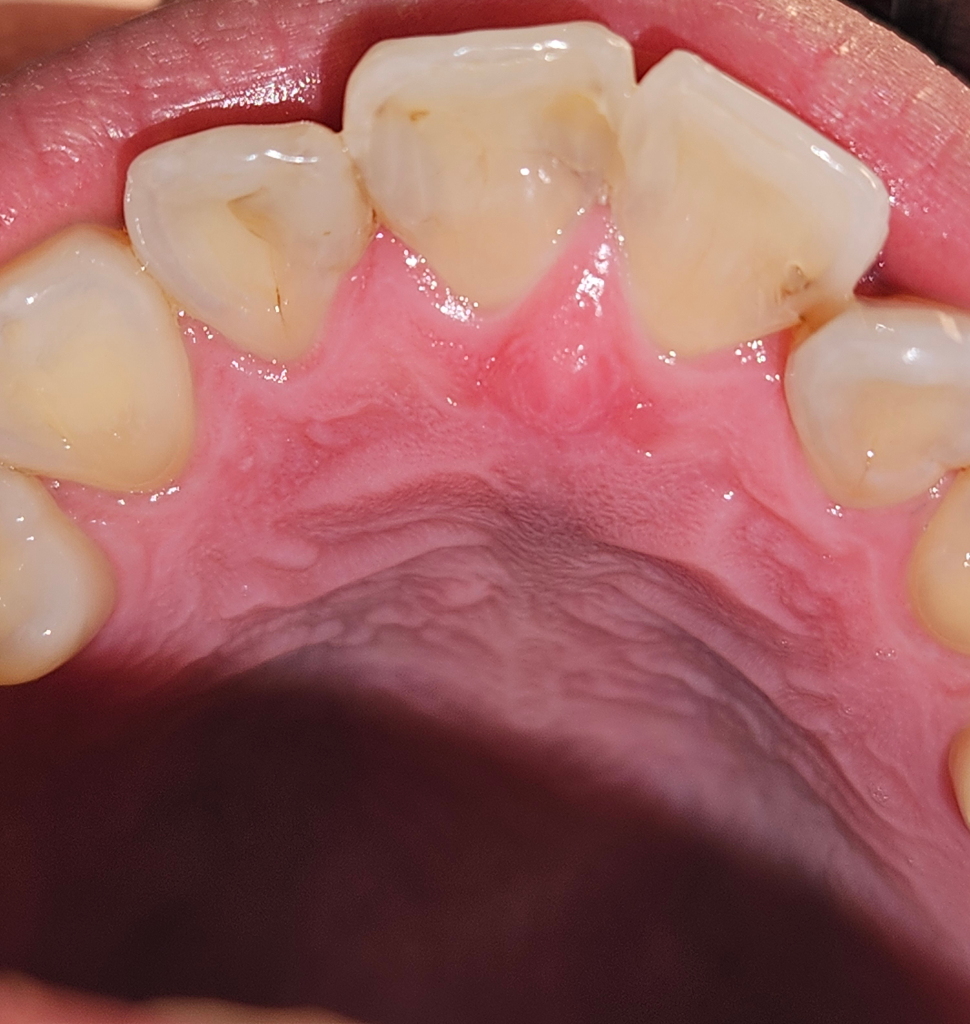

레진 충치 치료를 이렇게 치아 끼리 연결해 때우는게 맞나요?

치실도 안들어가게 두개를 연결해서 때워져있고

한쪽은 보면 레진이 다 채워져 있는거 같지도 않아요

이거 정상인가요?

따로 치아끼리 연결한다고 안내 받은적도 없고

치료 끝난 후 두텁게해서 뭐가 끼인 느낌 든다는 안내만 받았어요

지금 느낌은 치아 3개를 실로 묶어놓은 기분입니다.

• 3번 째 사진